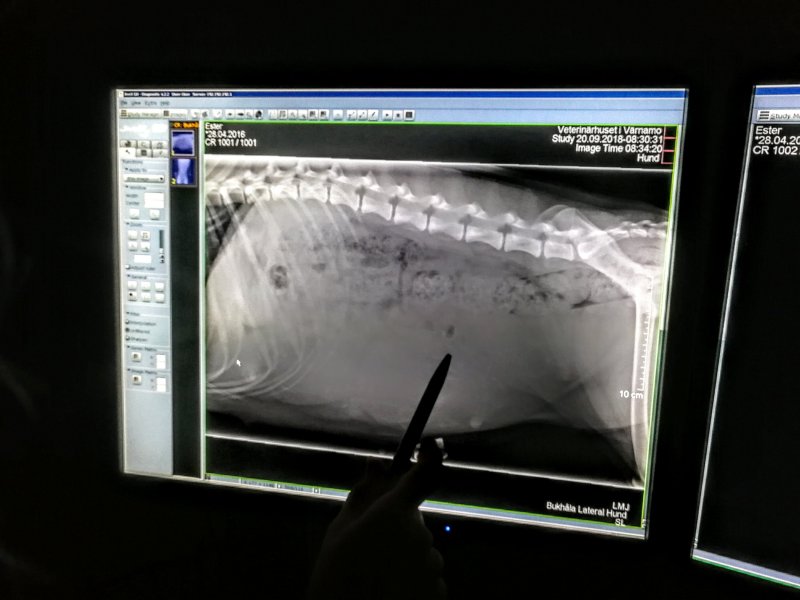

Ester skötte sig utmärkt under röntgen idag på morgonen. Tyvärr visade det sig att vi var lite för tidigt ute vilket gjorde att resultatet inte blev så tydligt som vi önskade. Vi kommer därför att göra en ny röntgen nästa torsdag vid 08.30 då vi hoppas på klara besked. Men visst är det valpar därinne. Frågan är bara hur många? Inget är som väntans tider. Men vad det är svårt att vänta!